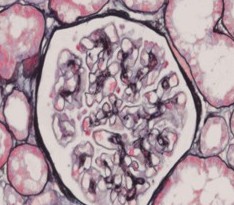

廣義的糖尿病腎臟病變包括感染性病變和血管性病變。感染性病變有腎盂腎炎和腎乳頭壞死。血管性病變分微血管和大血管病變,大血管病變包括腎動(dòng)脈硬化 (累及主干及分支)和腎小動(dòng)脈硬化(累及人球和出球小動(dòng)脈)。微血管病變是指腎小球硬化,分結(jié)節(jié)性、滲出性和彌漫性三種,三者可單獨(dú)可合并存在,上述改變中,最典型的是結(jié)節(jié)性腎小球硬化。我們通常說的糖尿病腎病是腎小球硬化。

Ⅳ期,病程在15-25年以上,約40%的T1DM患者發(fā)展到這一階段。病理上出現(xiàn)典型的改變,而診斷主要依據(jù)臨床表現(xiàn),尿蛋白排出量增多(>0.5g//24h),大多數(shù)患者出現(xiàn)高血壓,腎小球?yàn)V過率開始下降。有效的抗高血壓治療可減慢腎小球?yàn)V過率下降的速率。

V期,為終末期腎衰,特點(diǎn)是普遍的腎小球毛細(xì)血管閉塞,伴有腎小球玻璃樣變,腎小球?yàn)V過率已很低,氮質(zhì)潴留,高血壓明顯。